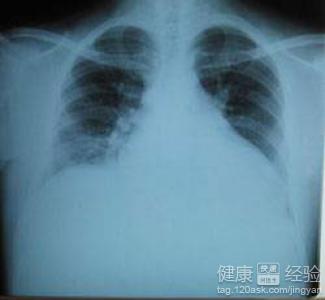

擴張性心肌病是一種人體的心肌疾病,此病主要表現在我們人體的左心室或者右心室擴大,有的也是兩側都擴發,並且還會有功能減退的現象,此病若是病情加重,很容易會使患者出現死亡。此外像服用了抗癌的藥物,或者精神受到刺激都可能會引起這個病。這個病比較常見的症狀有像呼吸困難,心律不齊等等,那麼在我們平常的生活中擴張性心肌病應該注意什麼呢?今天我就跟大家分享一下。